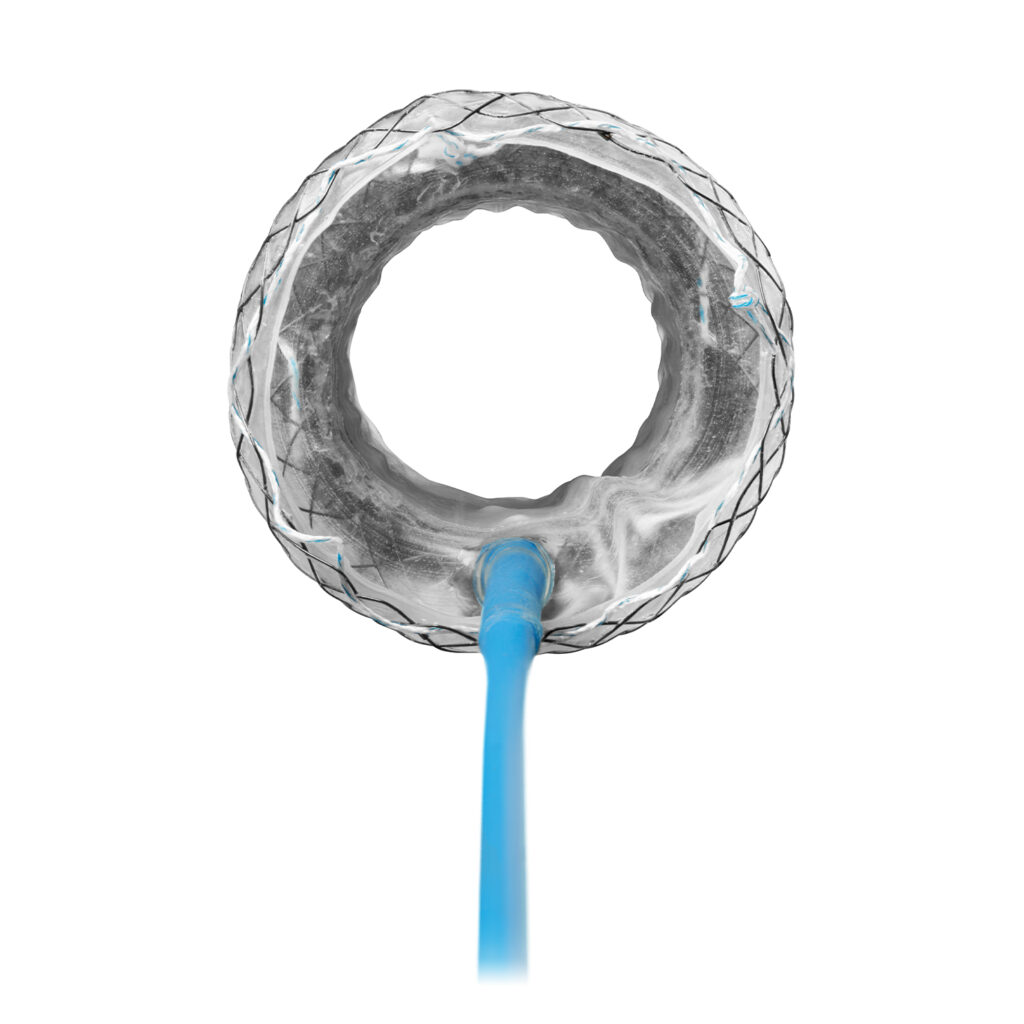

The VacStent GI™ combines two reliable methods for the treatment of leakage and anastomotic insufficiency: while the fully encased stent completely covers the defects, the wound cavity is drained by continuous suction.

- For leakages up to 30 mm

- Open passage and thus no feeding tube required